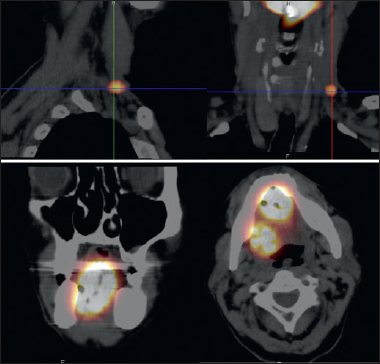

Pre-surgical dynamic and static scintigraphic images were collected using a single-head gamma camera (Starcam 4000 GE Medical System, Milwaukee, WI, USA). Tomographic images were obtained using a dual-head gamma camera (Millennium GE Medical System, Milwaukee, WI, USA). Both gamma cameras were equipped with a low energy collimator with high resolution.

Patients were placed in supine position with the head approximately in the same position as that of the surgery. Dynamic acquisitions started immediately after radiocolloid administration and continued for 15 minutes (30 frames/sec), while static images, in anteroposterior and lateral projections, were acquired 30 minutes and 2 hours following the injections. At the end of the lymphoscintigraphic procedure, the skin projection of the underlying enhancing lymph nodes was marked with India ink. Scintigrafic data were matched to CT images in order to achieve a topografic localisation of the interested lymphatic drainage on both coronal and axial CT scans (Fig. 1).

Figure 1. Preoperative detection of SPECT/CT lymphoscintigraphic enhancing lymph node.